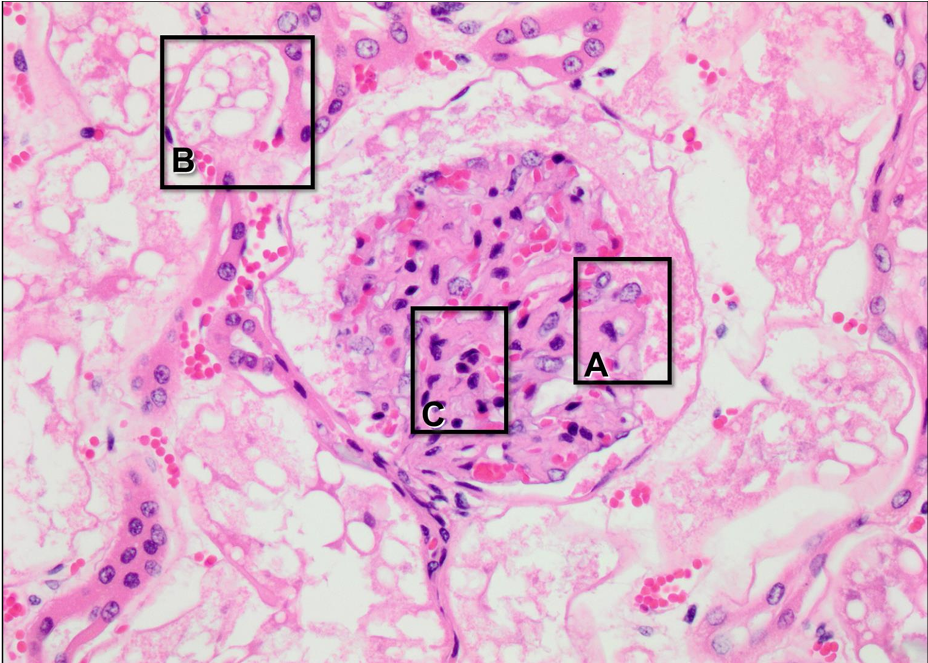

Tissue from a cat with proteinuria.

The diagnostic lesion is in which box?